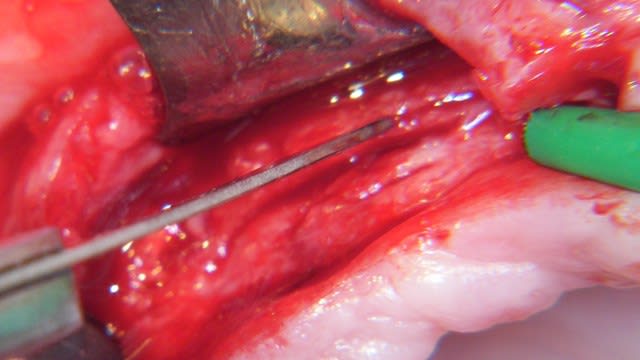

Un exemple de splitting sectoriel au maxillaire sup avec :

- piezo,

- osteotome,

- implant Astra osseospeed,

- comblement par mélange os autogène et BioOss,

- recouvrement par membrane BioGide + conjonctif palatin.

une question technique, le lambeau vestibulaire il est d'épaisseur totale ou partielle (conf la vascularisation du volet osseux déplacé)

en ce qui concerne les décharges osseuses, tu les descends jusqu'ou?

fragilises tu le volet osseux en apicale?

> une question technique, le lambeau vestibulaire il est d'épaisseur totale ou

> partielle (conf la vascularisation du volet osseux déplacé)

Très juste Dumaille. Le lambeau est d'épaisseur totale d'une part au niveau des incisions crestales verticales et sur toute leur hauteur et d'autre part jusqu'á la moitié de la hauteur du volet osseux. Le reste est en épaisseur partielle. Point important. Merci de l'avoir souligné.